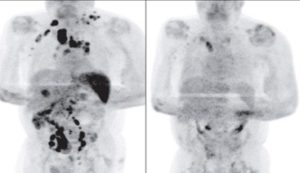

While both non-Hodgkin’s and Hodgkin’s lymphoma effect the lymphatic system, they often impact different parts of the system. Hodgkin’s lymphoma typically occurs in the lymph nodes found in the neck, chest, or underarms. From there, it often progresses in a predictable fashion moving from one group of lymph nodes to the next. Progressing in such an orderly fashion allows the cancer to be detected and treated at an early stage. Hodgkin’s lymphoma is recognized as one of the most treatable cancers, with over 90% of patients surviving more than five years. Non-Hodgkin’s, however, often arises in various parts of the body. It can surface in similar lymph nodes as Hodgkin’s lymphoma, or even in the groin and abdomen. Because of this, most cases of non-Hodgkin’s lymphoma is diagnosed at an advanced stage.